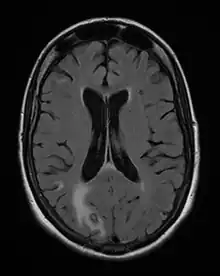

Acute toxoplasmosis is often asymptomatic in healthy adults.[13][14] However, symptoms may manifest and are often influenza-like: swollen lymph nodes, headaches, fever, and fatigue,[15] or muscle aches and pains that last for a month or more. It is rare for a human with a fully functioning immune system to develop severe symptoms following infection. People with weakened immune systems are likely to experience headache, confusion, poor coordination, seizures, lung problems that may resemble tuberculosis or Pneumocystis jirovecii pneumonia (a common opportunistic infection that occurs in people with AIDS), or chorioretinitis caused by severe inflammation of the retina (ocular toxoplasmosis).[15] Young children and immunocompromised people, such as those with HIV/AIDS, those taking certain types of chemotherapy, or those who have recently received an organ transplant, may develop severe toxoplasmosis. This can cause damage to the brain (encephalitis) or the eyes (necrotizing retinochoroiditis).[16] Infants infected via placental transmission may be born with either of these problems, or with nasal malformations, although these complications are rare in newborns. The toxoplasmic trophozoites causing acute toxoplasmosis are referred to as tachyzoites, and are typically found in various tissues and body fluids, but rarely in blood or cerebrospinal fluid.[17]

Diagnosis of toxoplasmosis in humans is made by biological, serological, histological, or molecular methods, or by some combination of the above.[62] Toxoplasmosis can be difficult to distinguish from primary central nervous system lymphoma. It mimics several other infectious diseases so clinical signs are non-specific and are not sufficiently characteristic for a definite diagnosis. As a result, the possibility of an alternative diagnosis is supported by a failed trial of antimicrobial therapy (pyrimethamine, sulfadiazine, and folinic acid (USAN: leucovorin)), i.e., if the drugs produce no effect clinically and no improvement on repeat imaging.